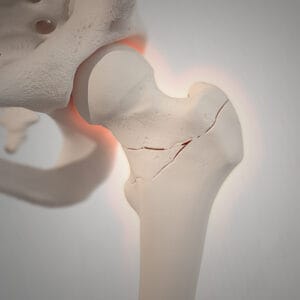

prelomi kuka